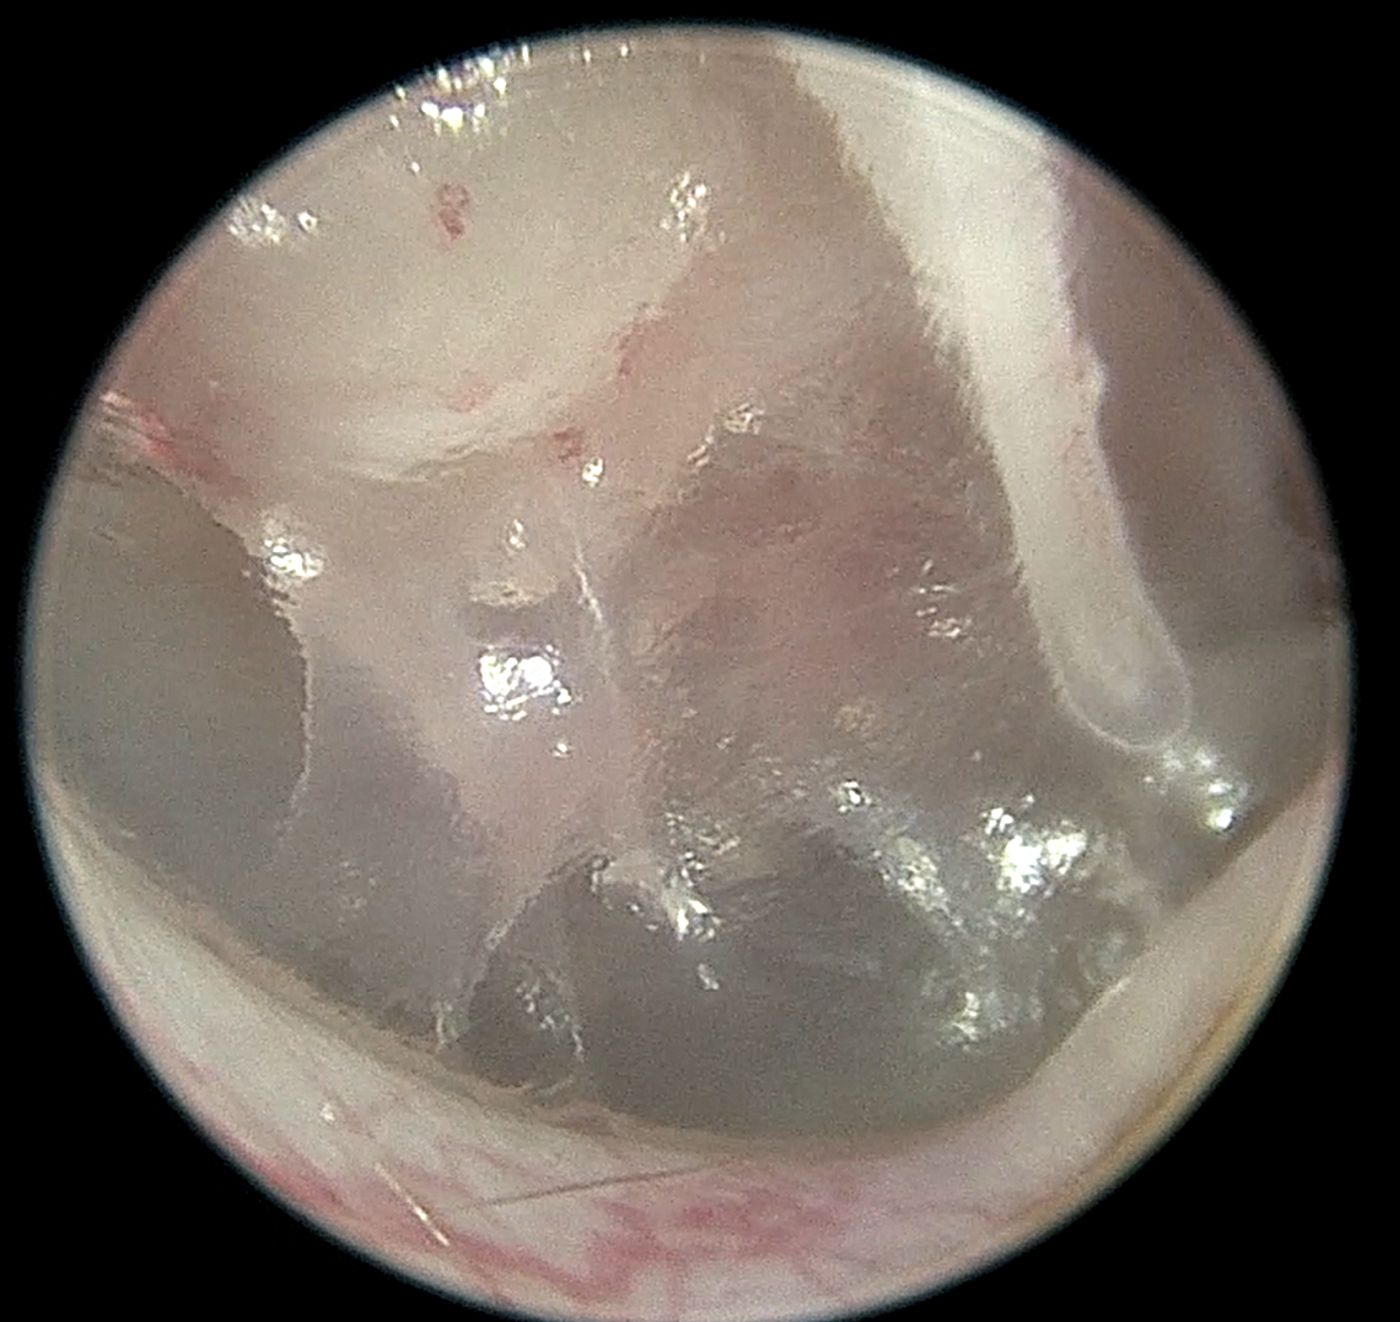

Diagnostyka endoskopowa zewnętrznych przewodów słuchowych (Otoendoskopia)

Głębokie płukanie przewodów słuchowych w znieczuleniu ogólnym

Myringotomia (nakłucie błony bębenkowej z oczyszczeniem z wydzieliny zapalnej) w celu diagnostyki i leczenia zapalenia ucha środkowego i wewnętrznego

Usuwanie ciał obcych (kłosy, bezoary)

Pobieranie biopsji tkanek zmienionych

Resekcję zmian nowotworowych w obrębie ucha zewnętrznego, także przy użyciu lasera